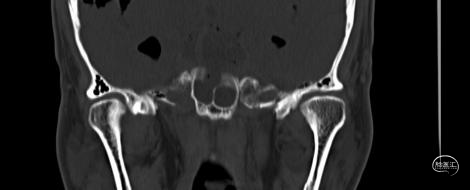

患者男性,65岁,在家中无明显诱因出现脑脊液鼻漏,呈清水样,伴头痛,坐位明显,平躺减轻,无其他特殊神经系统阳性体征。就诊时CT提示颅内广泛积气。

颅底CT三维重建提示未见明显骨折迹象,斜坡处骨质部分缺损可疑。